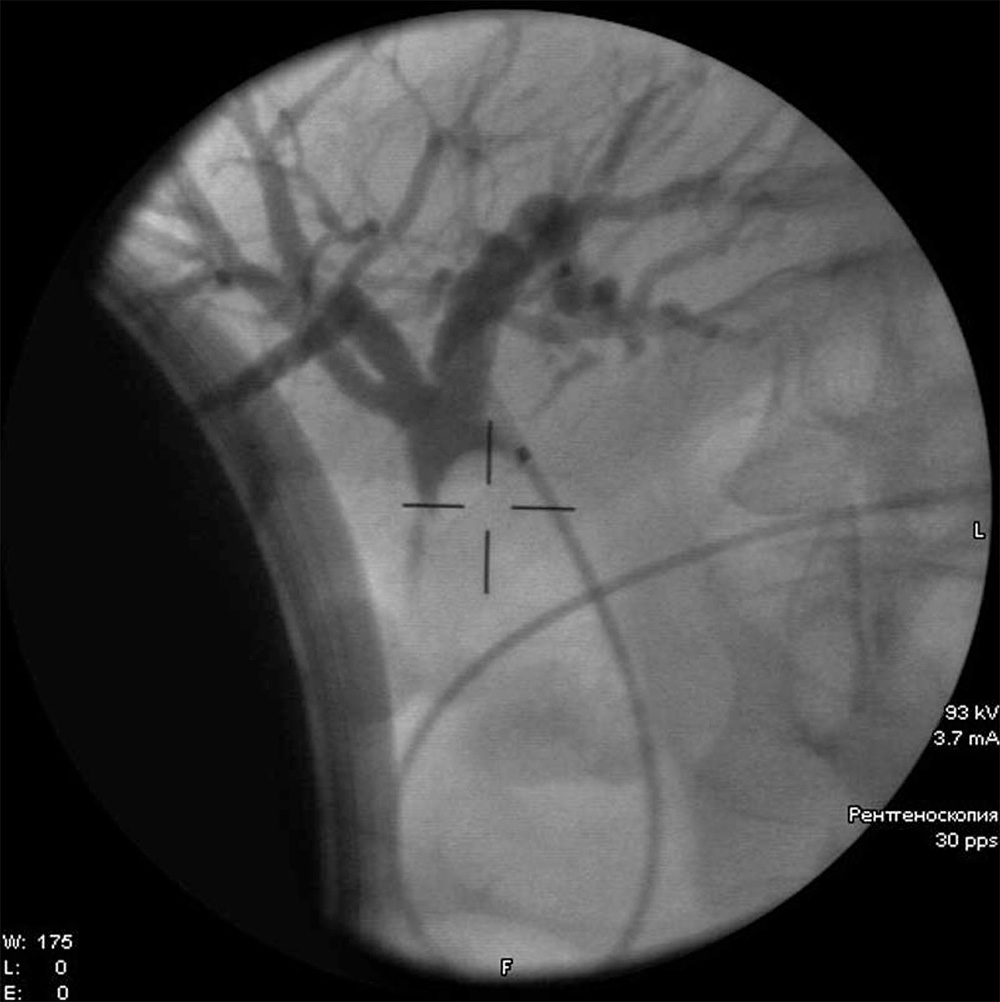

На 5-е сутки после первичного вмешательства и после констатации полного разрешения клинической картины холангита с применением аппарата Dornier Comact Delta II (Германия) был осуществлен один сеанс ДУВЛ, в ходе которого под рентген-навигацией на конкремент было осуществлено воздействие 3100 импульсов преимущественно максимальной интенсивности до 5 уровня (52,0 мПа, 0,72 мДж/кв. мм, 52,0 мДж, совокупная энергия 120,25 Дж). По завершении сеанса было отмечено лишь минимальное разрушение дистального края камня, заключавшееся в появлении некоторой нечеткости его контуров, и смещение конкремента в область общего печеночного протока при введении контрастного препарата (рис. 3).

Рис. 3. Крупный конкремент холедоха во время сеанса дистанционной ударно-волновой литотрипсии (ДУВЛ) (холангиограмма)